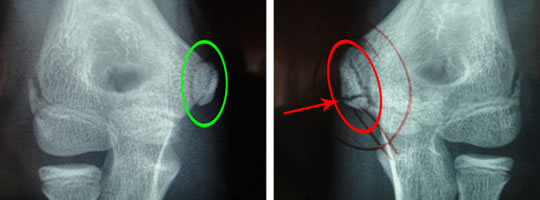

レントゲン画像(↓)、正面軽度屈曲位

注:左投げ選手

左肘内側の赤矢印先に横方向に黒い線があります。右肘にはありません。

拡大画像(↓):右肘(健側) 左肘(患側)